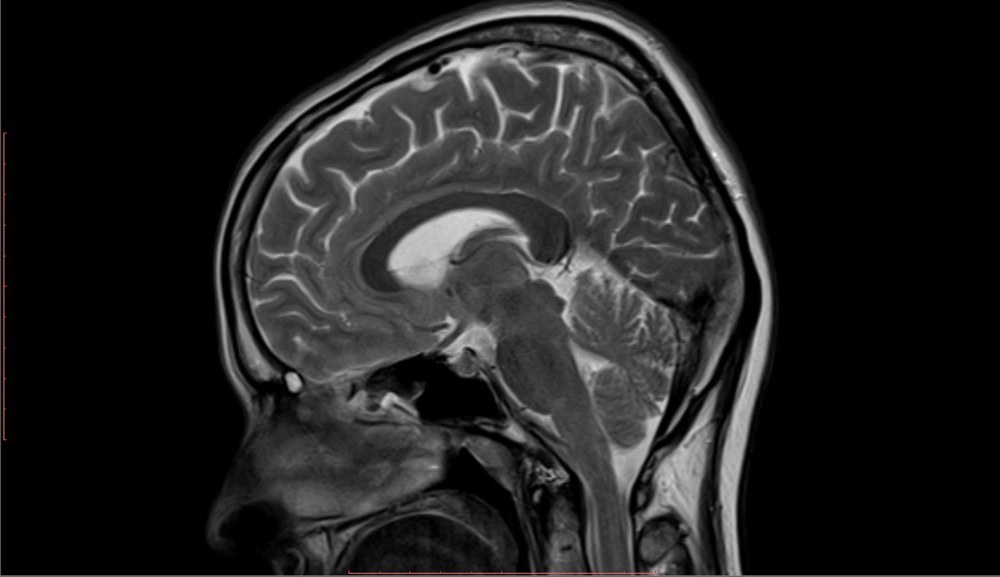

Pastebėjus kūdikyje galimus raidos ar neurologinius sutrikimus, gydytojas dažniausiai skiria tyrimus, kurie leidžia detaliau įvertinti smegenų struktūrą. Tuo tikslu atliekami ultragarsiniai, kompiuterinės tomografijos (KT) arba magnetinio rezonanso tyrimai (MRT). Tyrimų metu įvertinamas išorinės smegenų dalies lygumas ir griovelių storis.

Lissencefalijos sunkumas gali būti apibūdintas keliais lygiais. Pavyzdžiui, kai beveik visose smegenų dalyse nustatomas paviršiaus glotnumas (agyrija), kalbama apie pirmą sunkumo laipsnį. Tai labai retas atvejis, paprastai reiškiantis itin sudėtingą eigą ir stiprius raidos vėlavimus.

Daugumai vaikų būdingas trečias lissencefalijos laipsnis – tuomet priekinėse ar šoninėse smegenų dalyse matomas griovelių sustorėjimas (pachygyrija), o kitose vietose – paviršiaus lygumas.